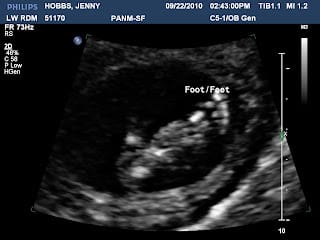

We are having another little boy! I wanted a little boy and later everyone was saying, "you are going to get a little girl" and I got excited looking at little dresses and pink nurseries and stuff. Yes, I knew it was going to be a boy, but I wanted a girl because they really don't sell a lot of cute clothes for boys and I wanted a princess room because I never had one, so I was going to live my dream through a baby girl. I think Heavenly Father sent me this cute little boy because he knew that if he sent me a girl, I was not going to have more children. Yes, I did the same things with this baby that I did when I found out that Mario was a boy... but to tell you the truth, I would never change my boys for a girl. The baby is fine, but the doctors need to monitor the baby closely so he won't get my Grave's disease, also the baby has a 4% chance to get pyloric stenosis, the same thing Mario had, remember that he got a surgery when he was a month old...